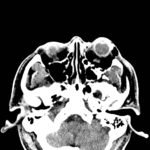

Physical exam showed marked left palpebral subcutaneous crepitus, as well as bulbar and palpebral conjunctival bulging. Visual acuity was normal with intact extraocular movements, and normal pupillary exam. Computed tomography (CT) imaging of the face was obtained and revealed multiple displaced fractures involving the left orbital floor and zygomatic arch associated with moderate periorbital and postseptal extraconal gas, resulting in orbital proptosis.